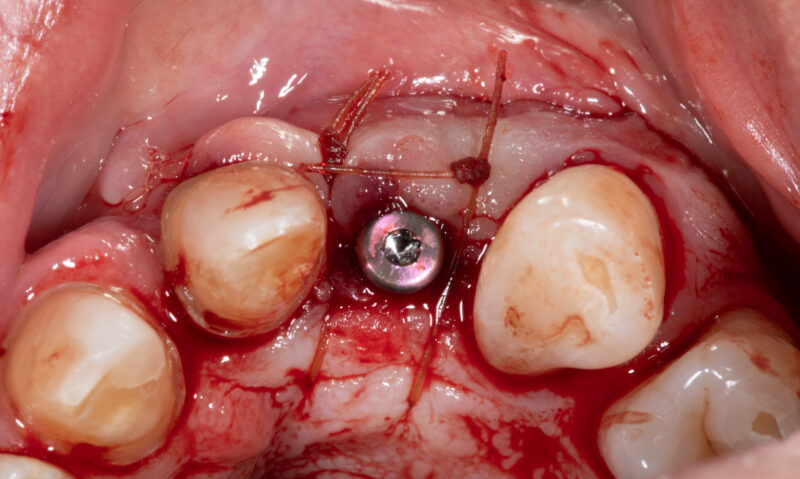

• Looks good, right?!? Not once you see the cbct and create a larger full thickness flap. What would you do here? What are your options? This happened during one of our live surgery courses. Please leave a comment below on what you would do and a couple options we may have. After I recieve several comments I will post a follow up post next week…

Read more

• implant position looks too buccal to me in this photo. i’d remove and start a new osteotomy and sink the implant to the level of the lingual bone

1